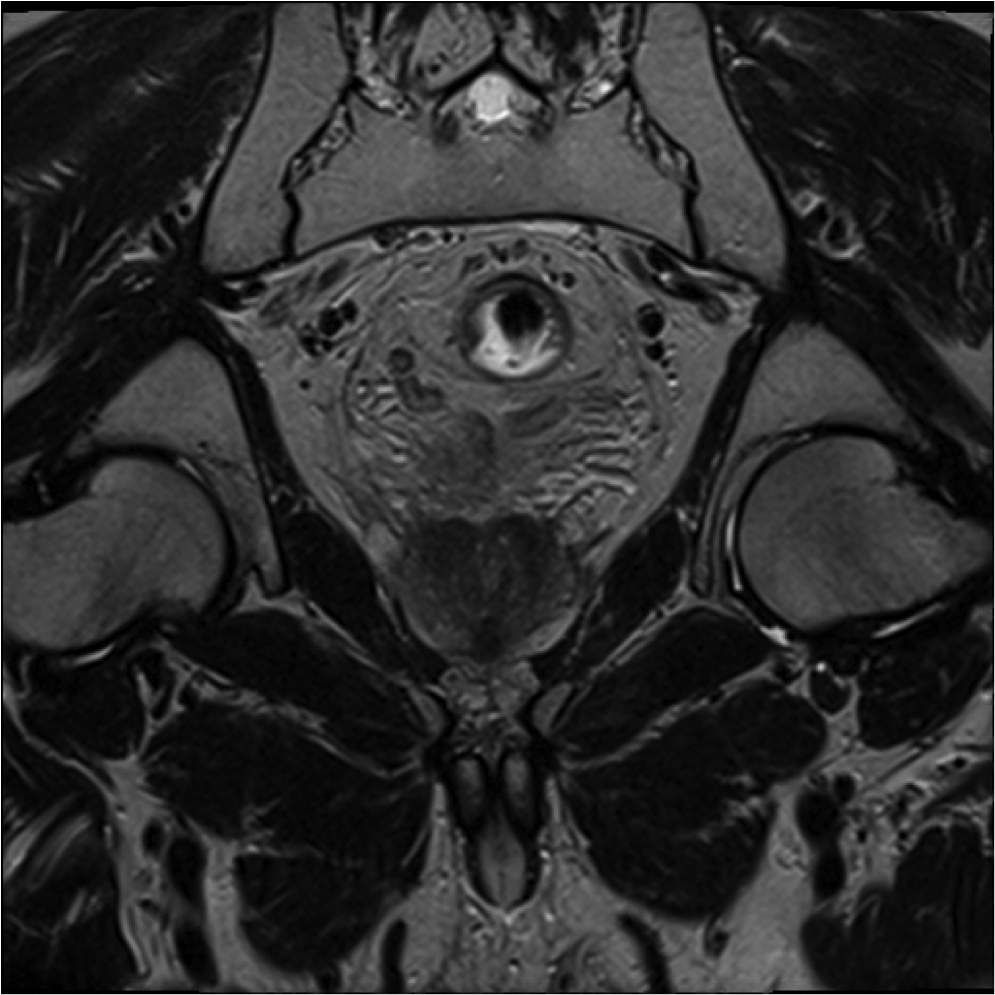

Fig.2. Același pacient post chimio-/ radioterapie – răspuns complet cu dispariția masei tumorale rectale; dispariția restricției de difuzie și reducere în dimensiuni a ganglionilor mezorectali; pacientul a beneficiat de TME şi s-a confirmat histopatologic absenţa ţesutului tumoral (pT0 pN0).

a-d) imagini T2 ponderate în 3 planuri

e) difuzie RM (b1000)

f) sagital T1 postcontrast